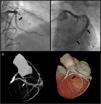

A 64-year-old Caucasian male with a history of coronary artery bypass grafting (CABG) [internal mammary artery (IMA) graft to the left anterior descending artery (LAD) and saphenous vein graft to right posterior descending artery (PDA)], presented with stable angina with a positive treadmill exercise test. Coronary angiography (CAG) documented occlusion of both middle LAD and IMA grafts (Figure 1, panel A); no significant lesions were found in the circumflex artery or the saphenous vein graft. The CAG performed prior to surgery is shown in Figure 2.

After a myocardial perfusion scintigraphy confirming viability in LAD territory, an angioplasty was performed. A new large vessel was visible after mid-LAD dilatation (Figure 1, panel B, supplementary film 1). The images were suggestive of a fistula or a shunt. A 4.0×18-mm drug-eluting stent was successfully implanted. The patient remained stable throughout the procedure.

CT angiography showed a fistula from the middle segment of the LAD to the coronary sinus (Figure 1, panel C). Excluding the fistula by implanting a covered stent was then considered. However, when performing the initial CAG, complete stent restenosis had occurred, resulting in both LAD and fistula occlusion (Figure 3). A silent infarction had probably occurred. A new ischemia test was performed, documenting necrosis without viability. A conservative approach was therefore chosen.